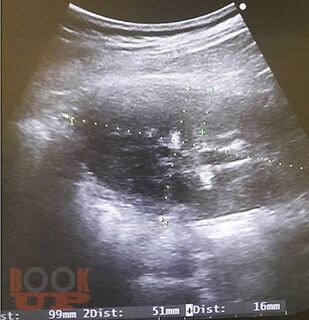

Пособие содержит материал, отражающий современные данные о лечебно-диагностических концепциях основных врождённых и приобретённых урологических заболеваниях взрослых и детей. В пособии раскрыты ключевые позиции, этиологии, патогенеза, классификации, клинических проявлений, диагностики, консервативного и хирургического лечения, возможных осложнений и исходов урологических заболеваний. Сделан акцент на эмбриопатогенез и пренатальную диагностику врождённых аномалий развития органов мочевыводящей системы у детей. Пособие содержит перечень вопросов для самоконтроля, тестовые задания и ситуационные задачи.